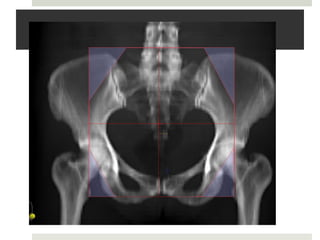

DRR LAT & AP Fields#33

3D PLAN

Bowel sparing